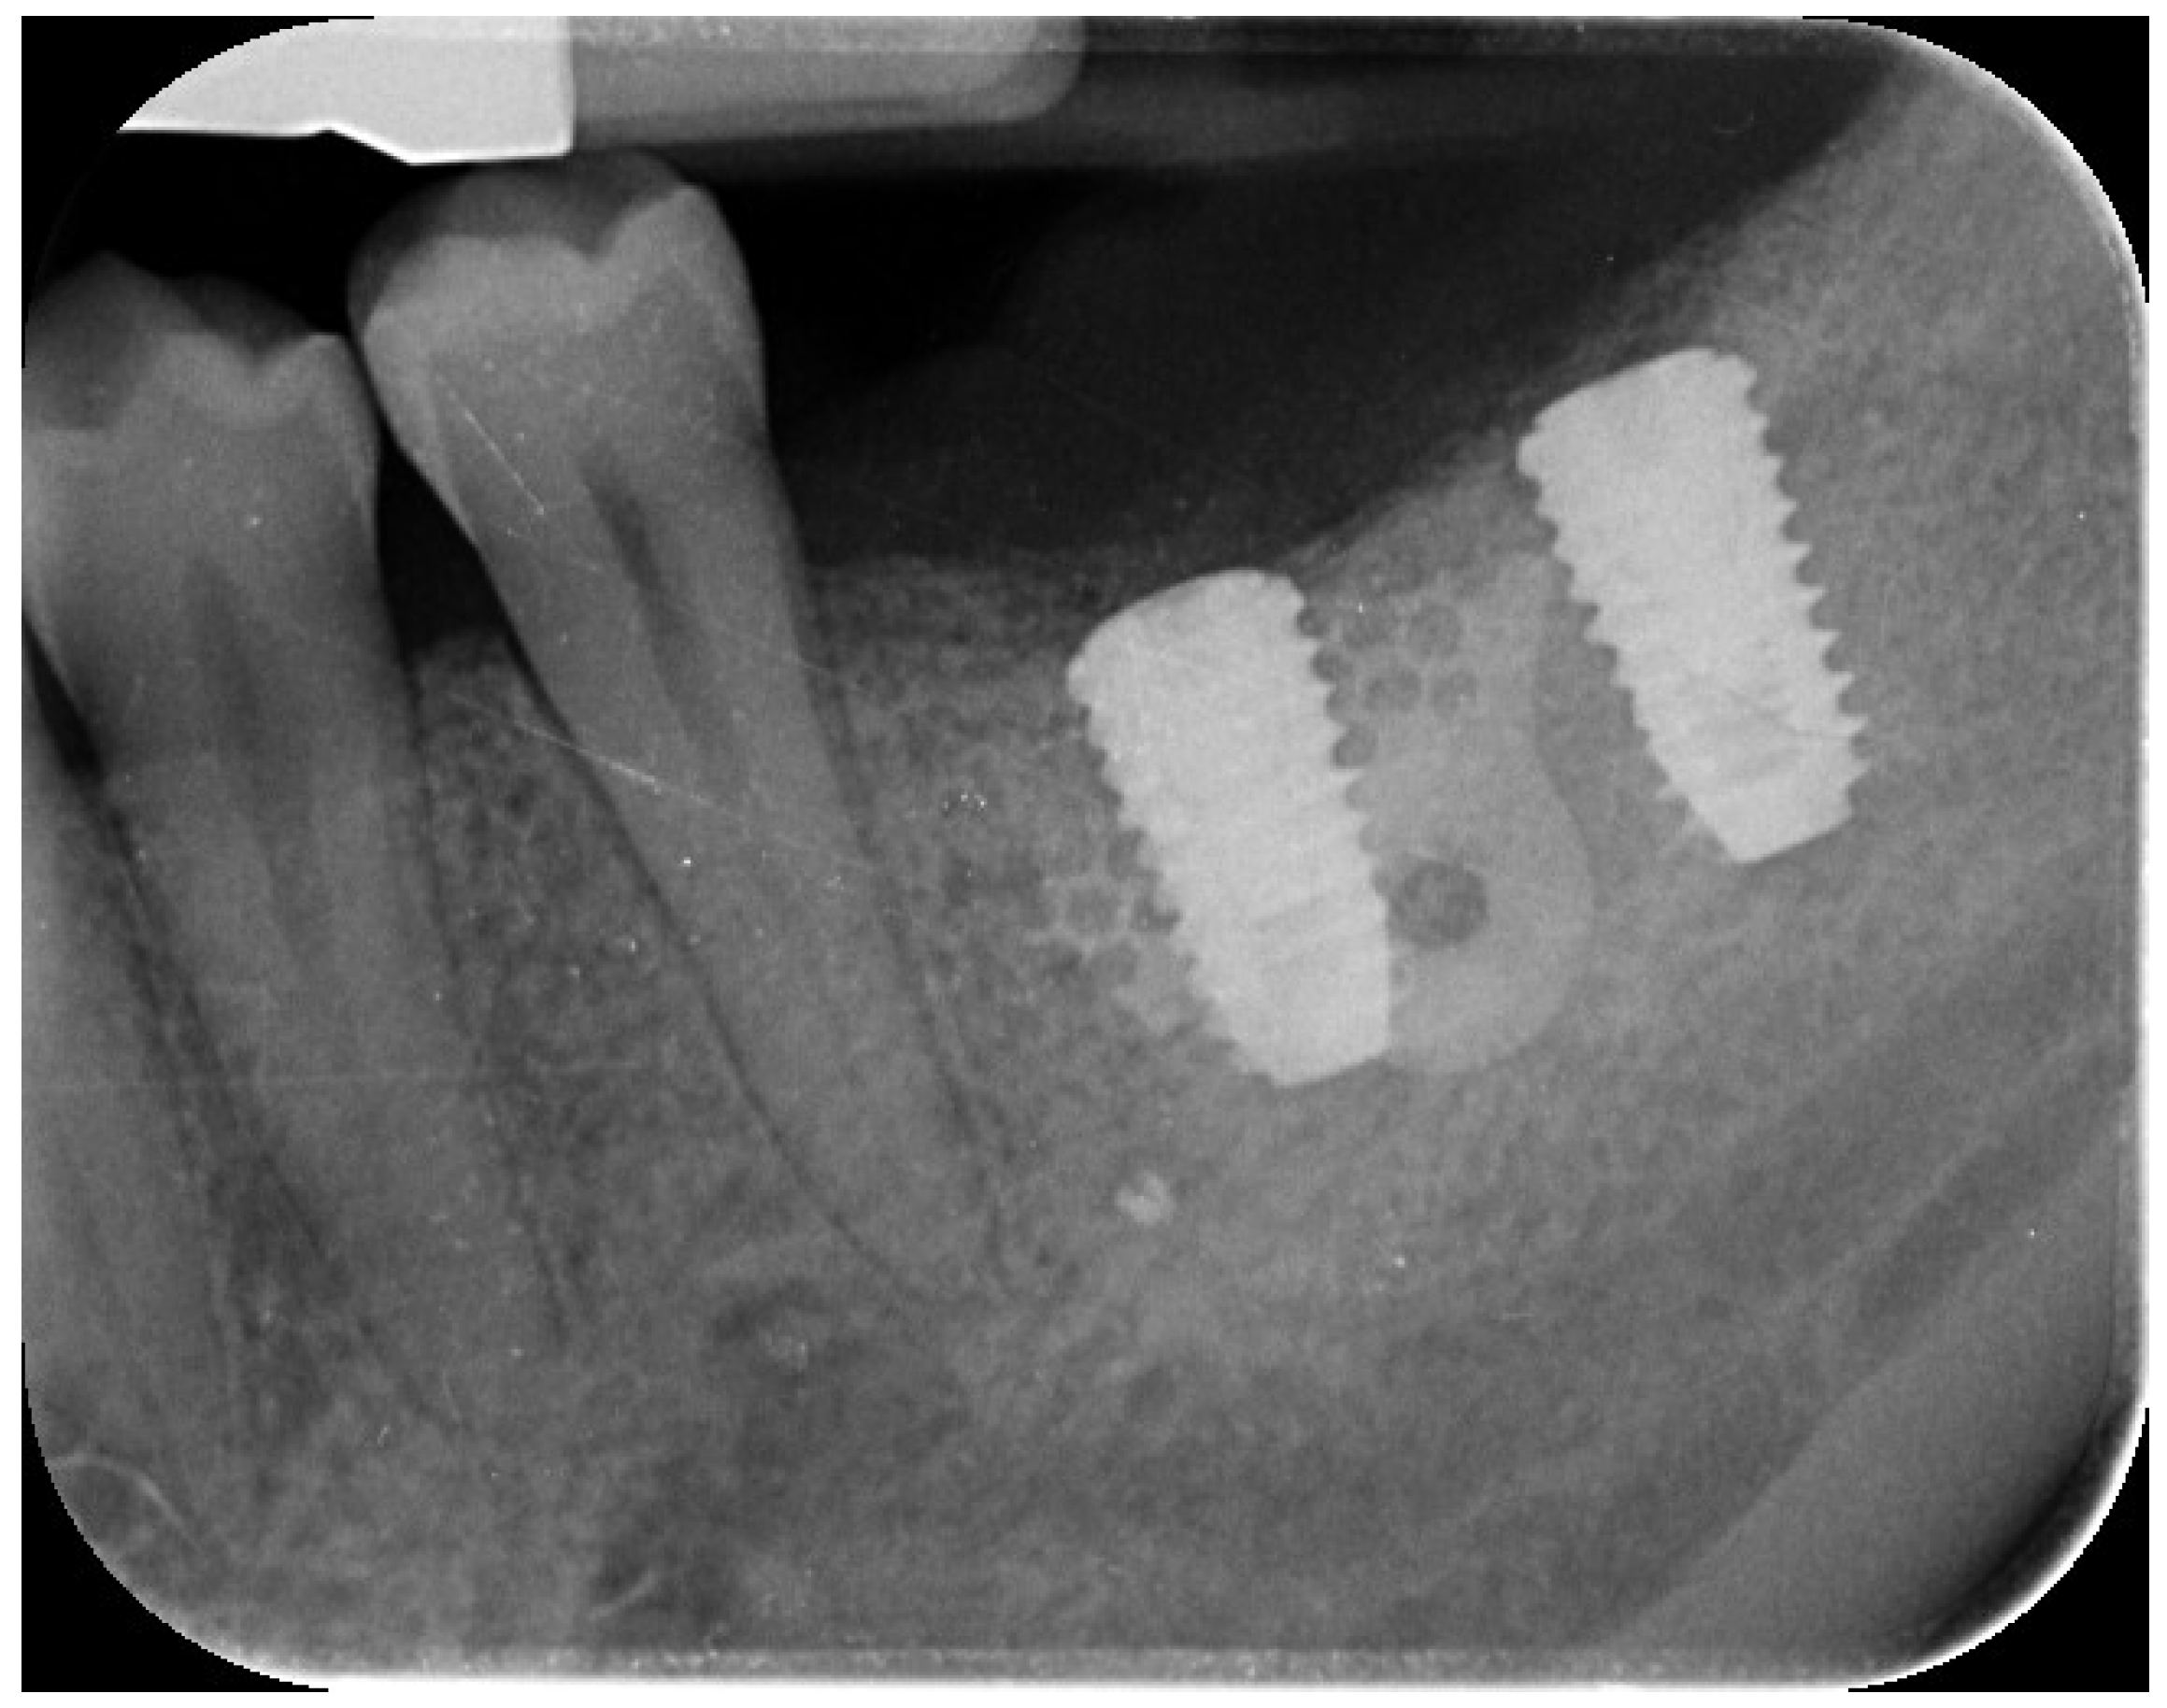

2. Case Summary